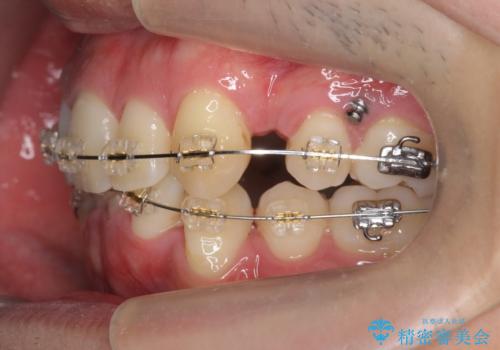

- ワイヤー矯正

上下左右の小臼歯を抜歯しています。

下のがたつきが大きいため、抜いたスペースをしっかり利用して並べるため矯正用インプラントを使用しています。